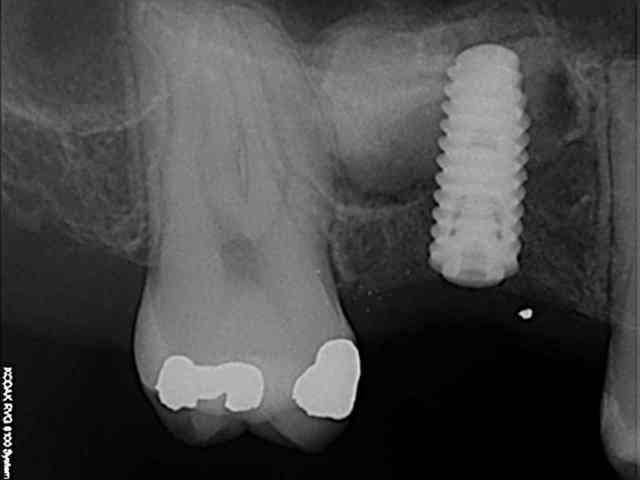

pour votre plaisir mon ami 8 mois d'écarts

fenêtre fermée par du vitalos pas de membrane technique "grosse ouverture"